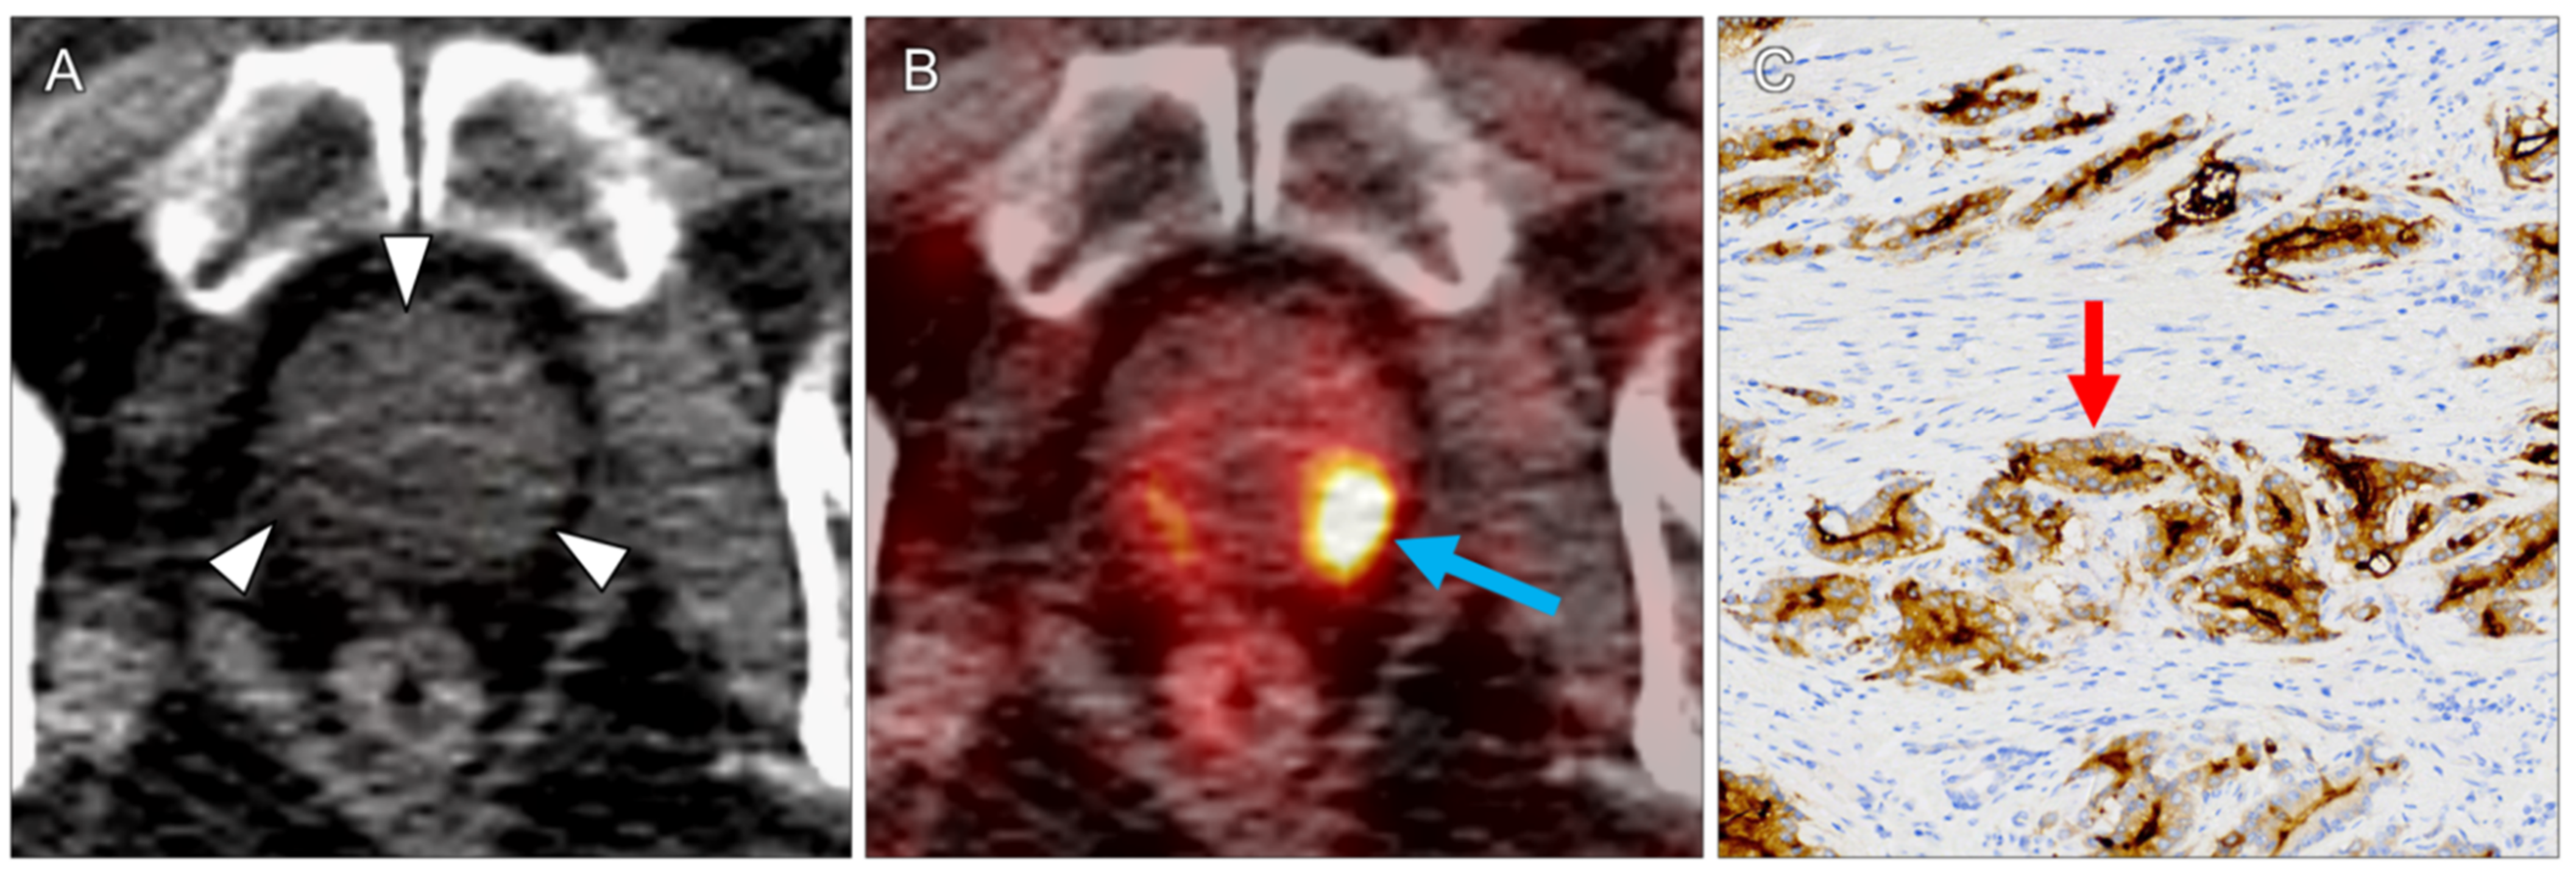

| 1 | mediastinal lymph node | 1.8 | 1.2 | 5.9 | 4.4 | 7.4 | 2 | ccRCC | 2 | 2 | 3 | 2 |

| 10 | right adrenal gland | 1.2 | 0.9 | 7.7 | 4.9 | 7.7 | 2 | ccRCC | 3 | 3 | 3 | 3 |